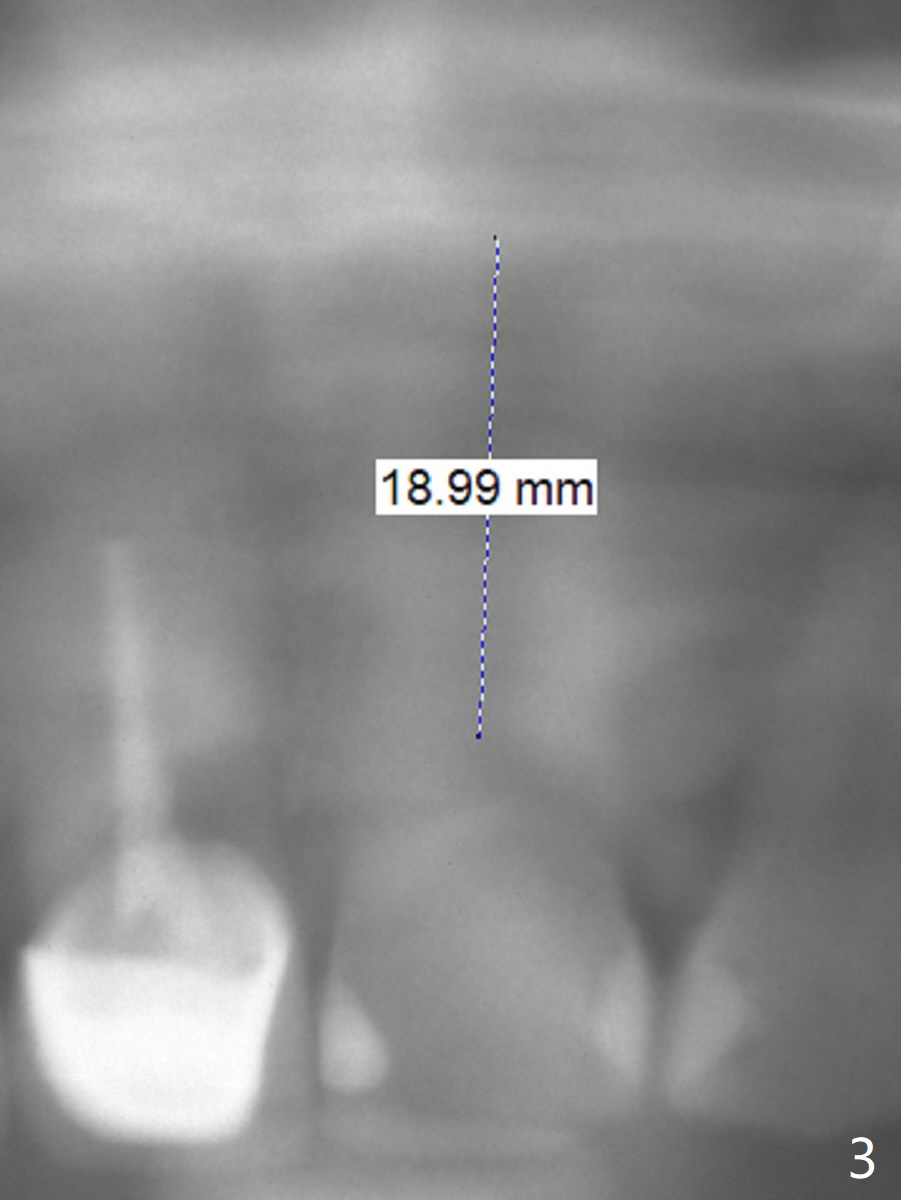

A 54-year-old man appears to be a unilateral masticator because of missing #30 (Fig.1). The left central incisor seems to have root fracture (Fig.2). To counter heavy occlusal force, a long implant will be placed (Fig.2,3).